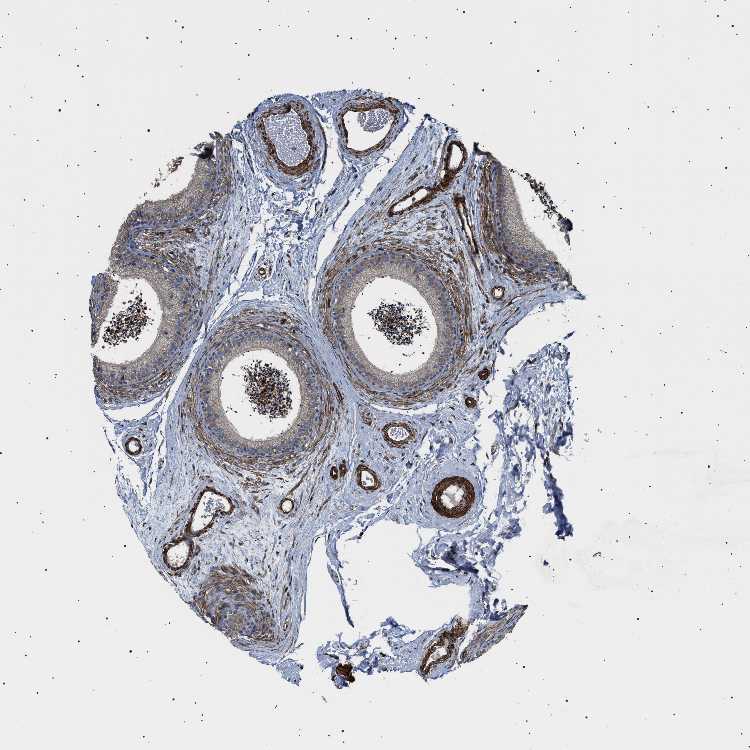

TISSUE PRIMARY DATA EPIDIDYMIS Show tissue menu

EPIDIDYMIS - Antibody stainingi

Antibody staining in the annotated cell types in the current human tissue is reported as not detected, low, medium, or high, based on conventional immunohistochemistry profiling in selected tissues. This score is based on the combination of the staining intensity and fraction of stained cells.

Each image is clickable and will lead to virtual microscopy that enables deeper exploration of all samples and also displays staining intensity scores, fraction scores and subcellular localization as well as patient and tissue information for each sample.

Antibody HPA020386

Glandular cells Low